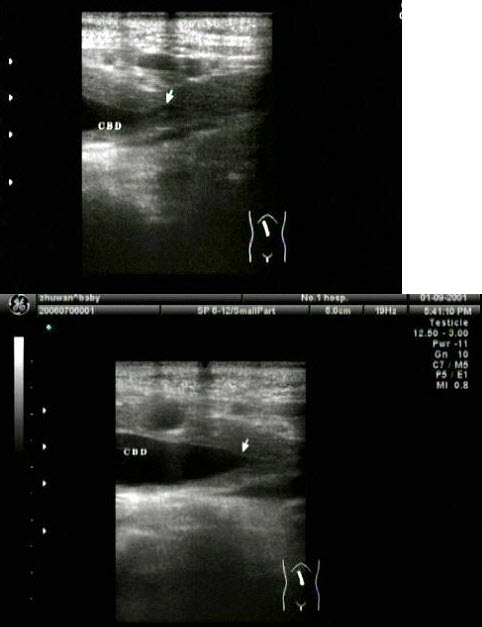

33、单项选择题

胆总管出现图中所示特点,称为()

A.双筒枪征

B.海鸥征

C.鸟嘴征

D.鼠尾征

E.平行管征